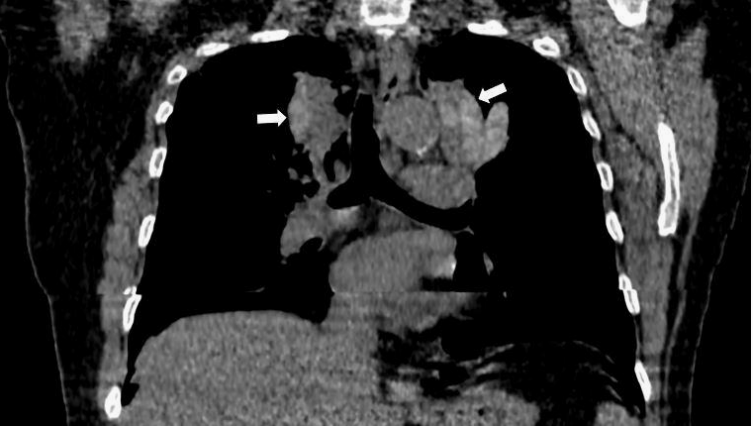

胸片:显示不均匀的放射性阴影,累及气管旁两侧上部区域,呈V形。右肺门增大,右肺门旁可见类似的放射性阴影,主要累及右肺中叶,显示典型的手套指征(图1)。

图1 不均匀的放射性阴影(白色箭头),累及气管旁两侧上部区域,呈V形,右肺门增大,右肺门旁可见类似的放射性阴影(黄色箭头)